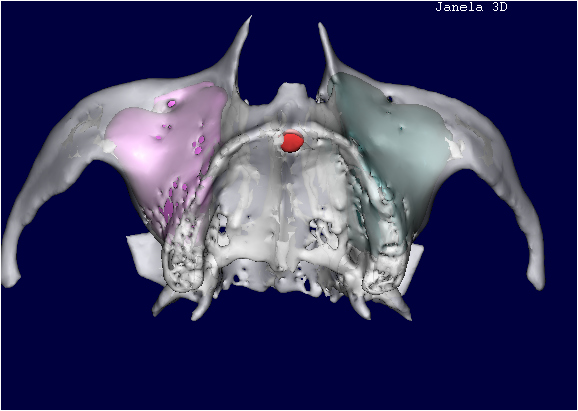

TOMOGRAFIA COMPUTADORIZADA ANTES DO ENXERTO ÓSSEO